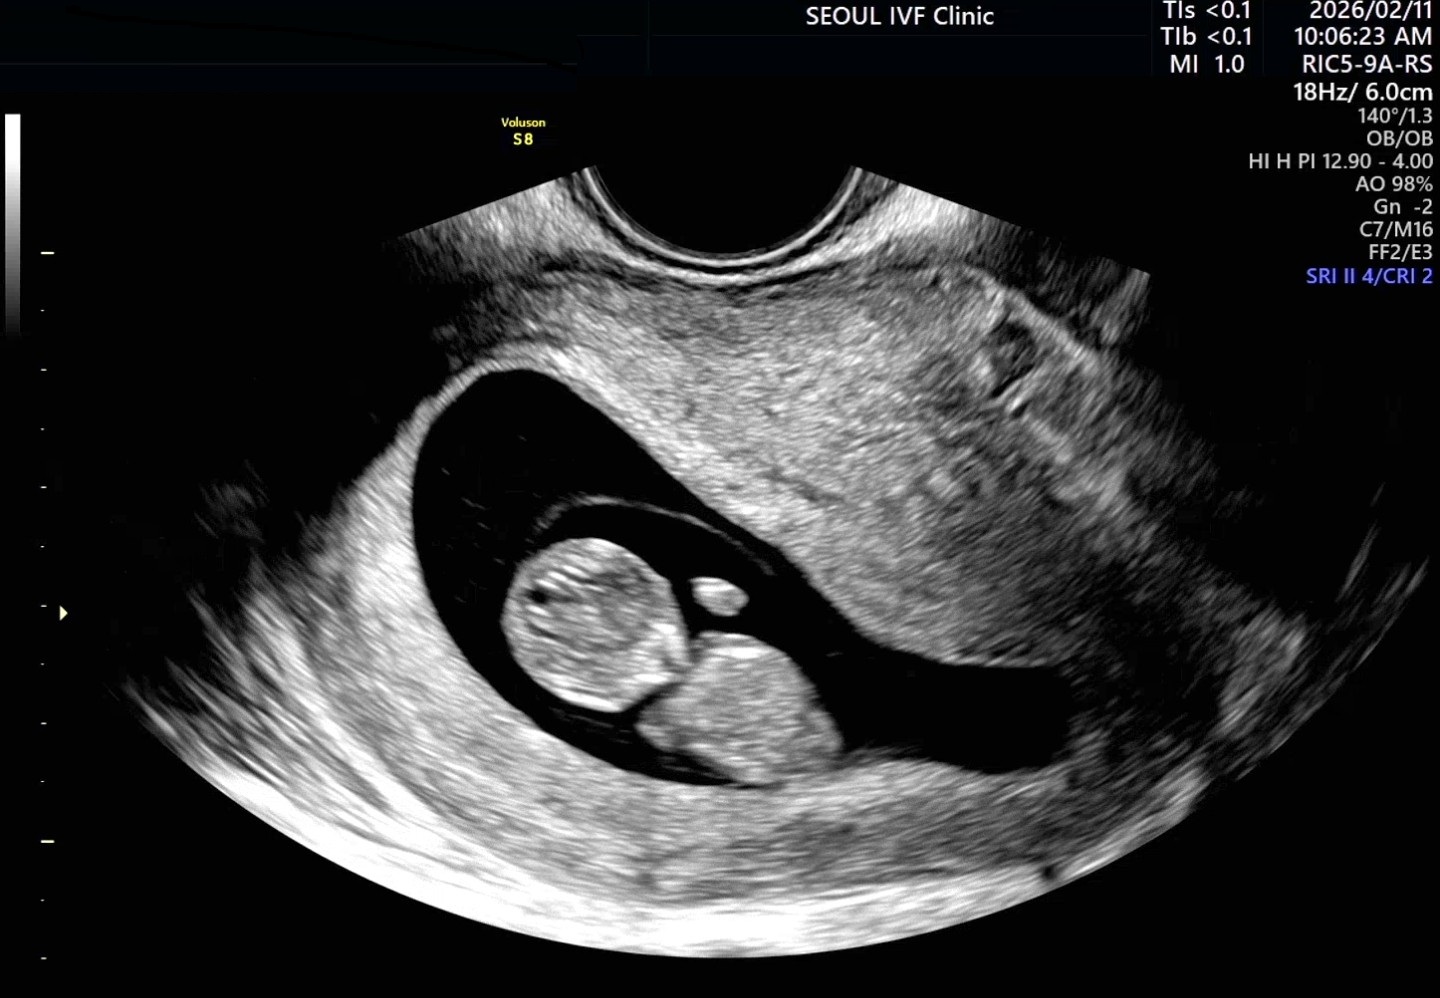

| 가슴 떨리는 임신 이야기를 공유해 주세요. | 여러 병원을 알아보고 선택하는 과정부터 치료를 이어오는 시간까지, 정신을 지켜내는 모든 순간들이 주마등처럼 지나갑니다. 대형병원이나 아파트와 제휴된 병원 등 다양한 병원 상담 끝에 객관적인 피드백과 경력 등에 확신이 들어 이경훈원장님을 선택하게 되었습니다. 그리고 1년이 안되는 시간동안 믿고 따랐고 좋은결과를 받게되어 기쁩니다. |

| 서울IVF여성의원의 난임 치료에 대해 말씀해 주실 것이 있나요? | 정말 추천드립니다. 환자가 많은 상황에서도 이름을 기억해 주신 점이 인상 깊었고, 제 자궁 특성을 고려해 모의시술까지 진행해 주신 섬세한 과정이 큰 신뢰로 이어졌습니다. 특히 세심한 접근이 필요한 분들께 추천드리고 싶습니다. |